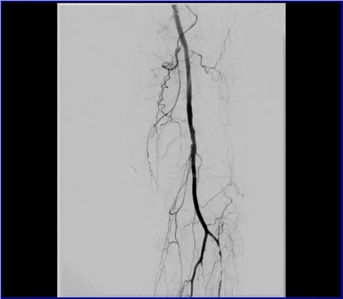

動脈閉塞處支架植入